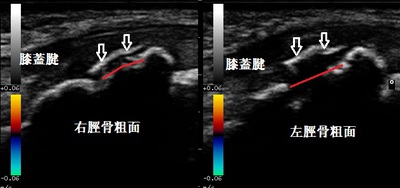

川越市 小学生 膝関節の痛み、オスグッドひざ

川越市 小学6年生男子、サッカークラブチーム所属。 左右膝関節の痛み、オスグッドひざ。

【原因】

サッカーの試合中に思いっきりボールを蹴ったところ、お皿の(膝蓋)骨の下に激痛が走りました。

前日のランニング中にも膝に痛みがありましたが、あまり気になりませんでした。

超音波検査を実施したところ、左右の脛骨粗面(膝蓋骨の下部)の軟骨が上画像の赤線の位置から

矢印の位置まで剥離している様子が認められました。

【治療】

オスグッドひざは成長期である小学高学年から中学生によく見られます。特にスポーツクラブチームや

運動部に所属している学生で、筋肉や関節が硬くなっている状態の時に発生しやすくなります。

オスグッド膝の痛みは剥がれた軟骨が骨癒合し、膝周囲の筋肉が充分柔軟になって痛みが消失します。

治療では剥離した軟骨を骨折の治療器を使用して骨癒合を促進させます。

また、硬くなった筋肉を手技マッサージで柔軟にしていくことで膝の屈伸をしても痛くない状態に

施術していきます。運動制限を極力しないで2か月後の骨癒合を目指していきます。